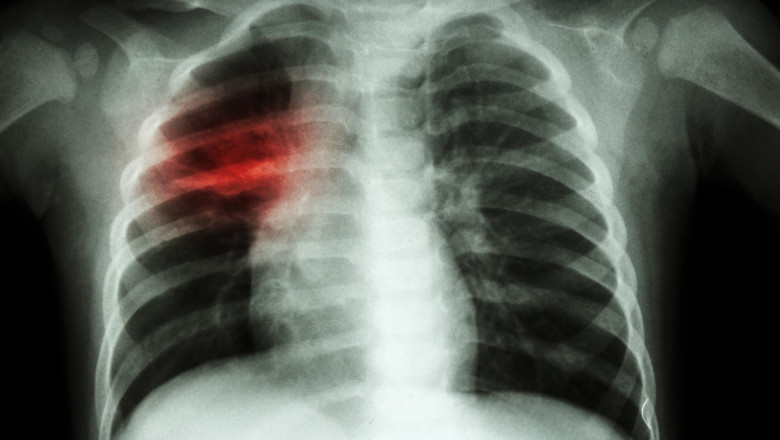

TBC este una dintre primele 10 cauze de deces la nivel mondial și reprezintă o infecție bacteriană potențial fatală care afectează în principal plămânii, fiind transmisă prin tuse sau strănut.